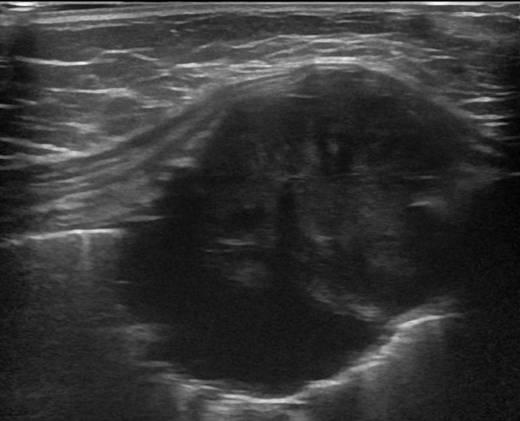

Di căn thành ngực

» Thông tin: Nam giới – 64 tuổi.

» Lâm sàng: Khối thành ngực / K vòm.